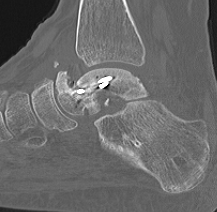

CT

Talus ACN CT 1Talus AVN CT 2